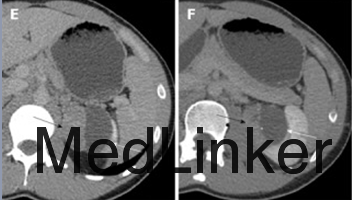

查体:左肾区叩痛(+),腹部无明显压痛、反跳痛,余未见明显异常。 辅查:我院腹部CT平扫+增强示:左肾囊实性肿块,大小约68X42mm,实性部分增强后在皮髓质期明显强化,后强化减低,囊性部分未见明显强化,考虑左肾恶性肿瘤并囊性变。余实验室检查未见明显异常。

入院诊断:左肾肿物:左肾癌?入院后行左肾肿物切除术,术中见一类球星肿物位于左肾下极,大小约6x5x4cm,颜色较正常肾实质深,质韧,表面较光滑,边界尚清晰,无明显粘连。术后病理示:(左肾盂旁肿物)肾类癌。